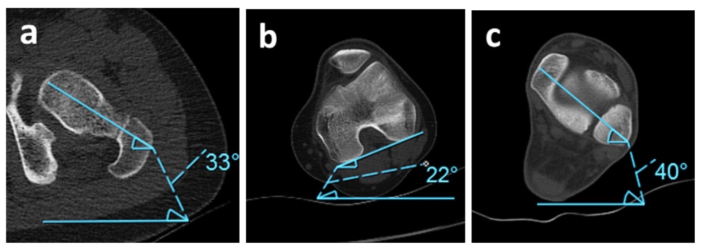

CT và MRI

MRI và CT với khả năng dựng hình 3D là các phương pháp tương đối chính xác để chẩn đoán biến dạng xoay ở chi dưới. Các đo lường được lấy từ các nhát cắt 2D qua cổ xương đùi, đầu dưới xương đùi, đầu trên xương chày, và gọng khớp cổ chân để xác định mức độ xoay. Có nhiều kỹ thuật đo lường đề nghị cho mỗi phân đoạn tùy theo các tác giả. Việc sử dụng CT nhiều lần có thể bị hạn chế ở trẻ nhỏ do tia xạ, ngược lại MRI lại đắt tiền và tốn thời gian hơn mặc dù không gây nhiễm xạ cho trẻ.